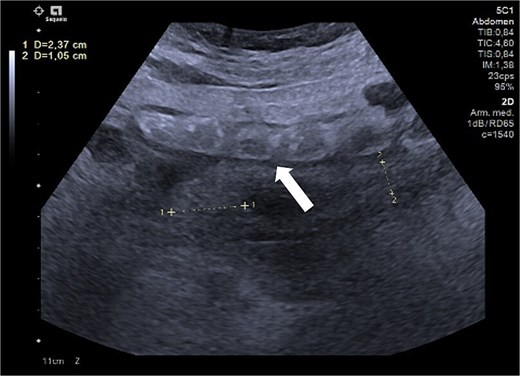

An abdominal ultrasound suggested AA (Fig. 1), prompting an open appendectomy. Intraoperative findings included cecal induration with distorted anatomy, thickened parietal peritoneum, 100 mL of ascitic fluid, and macronodular lesions on the peritoneum and intestines. Consequently, the appendectomy was not performed, and only a peritoneum biopsy and ascitic fluid sample were obtained for analysis.

Ultrasound of the right iliac fossa showing the cecal appendix (arrow), measuring 1.1 cm in diameter with a wall thickness of 0.34 cm. It demonstrated increased vascularity and non-collapsibility with compression.